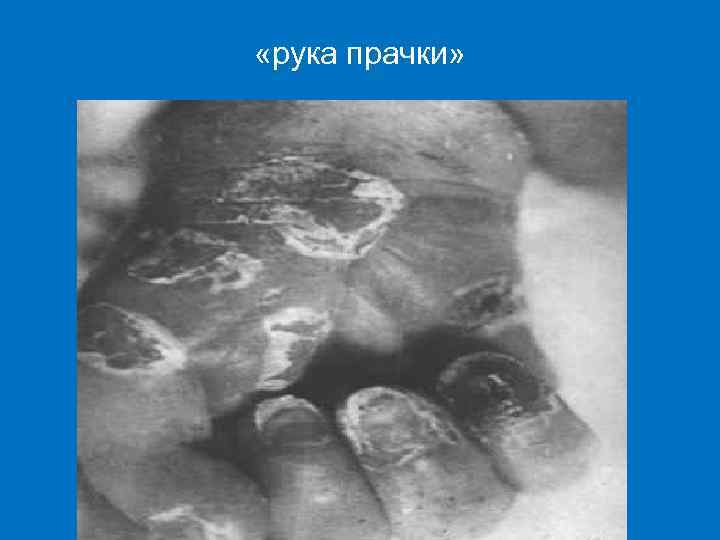

ДИФФУЗНАЯ ПАПУЛЁЗНАЯ ИНФИЛЬТРАЦИЯ § Локализация – ладони и подошвы, лицо, ягодицы, задняя поверхность бедер и голеней. § Кожа ладоней и подошв инфильтрируется, складки сглаживаются. § Цвет синюшно-красный, поверхность блестящая, «лакированная» , теряется эластичность, появляются трещины ( «рука прачки» ). § Процесс заканчивается крупнопластинчатым шелушением. § Инфильтрация Гохзингера: за счет растяжения при крике, сосании, на коже и слизистой оболочке вокруг рта образуются глубокие радиальные трещины после заживления которых образуются «лучистые рубцы» Робинсона– Фурнье.

«рука прачки»